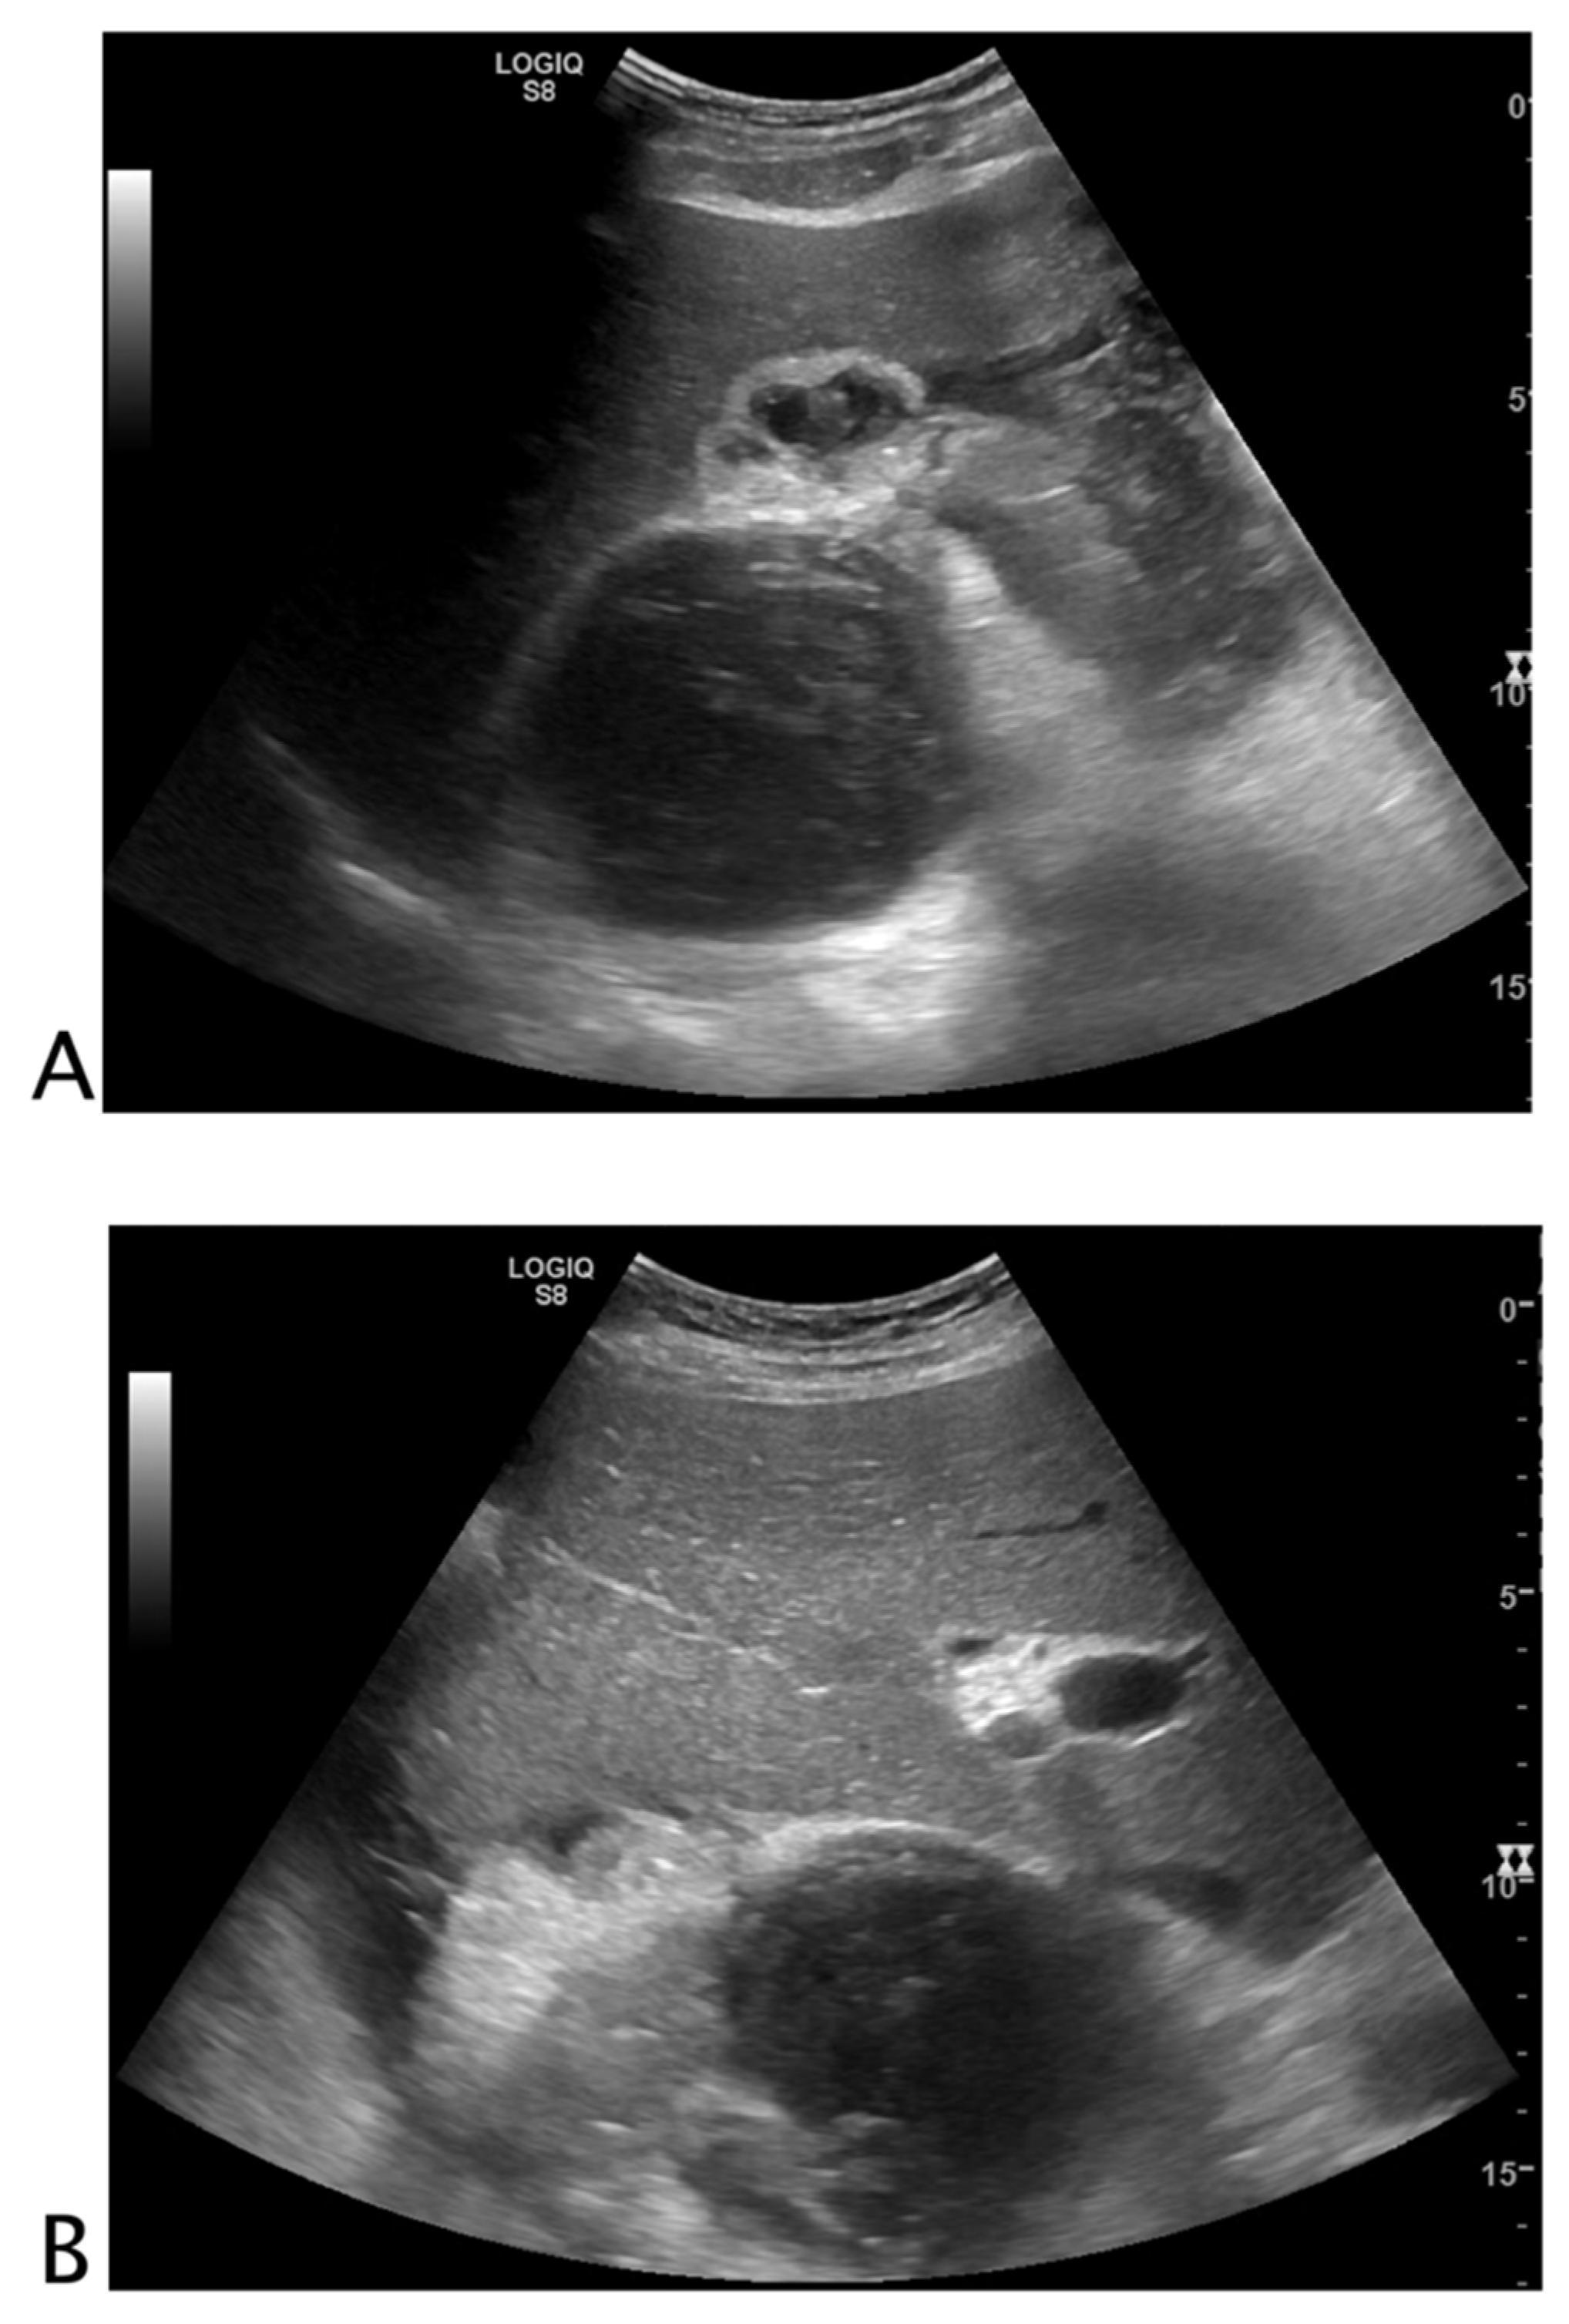

Intraparenchymal Fluid Lesions

| Intraparenchymal | Infected cyst Infectious cyst Hematoma Abscess Aneurysm Pseudoaneurysm |